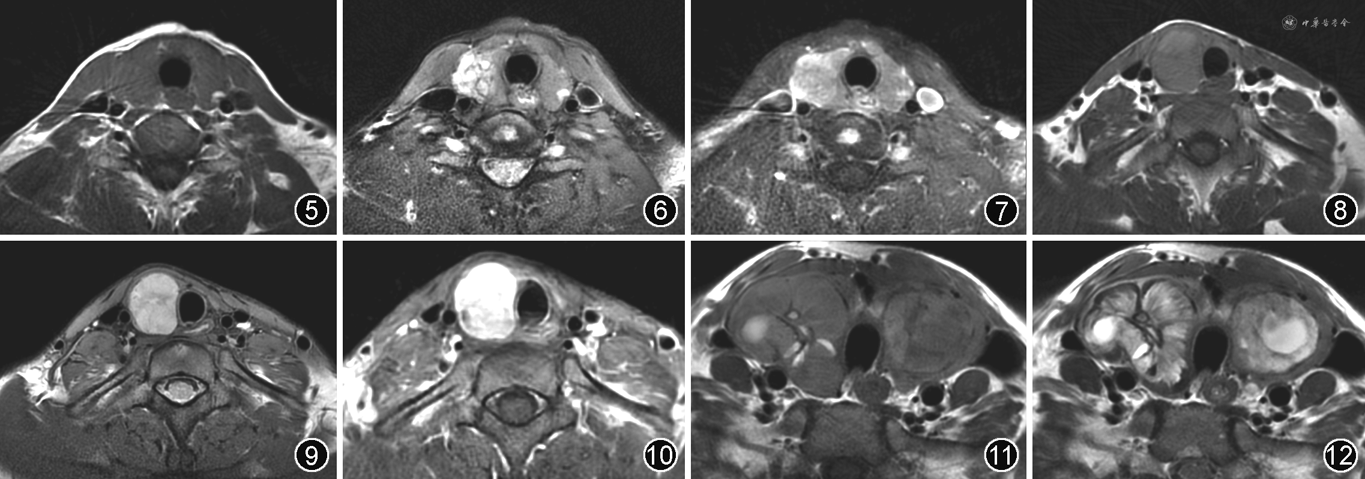

甲状腺癌MRI表现多为单发、形态不规则、瘤周不连续包膜样低信号、T2WI信号不均匀、囊变少[26],其中瘤周不连续包膜样低信号是甲状腺癌的特征性表现(图5~10)。

甲状腺癌大多信号不均匀,其信号与瘤内成分密切相关,若以细胞成分为主,则T1WI多呈等信号(图5),T2WI呈不均匀稍高信号;若以纤维成分为主,则T1WI呈稍低信号,T2WI多呈不均匀等或稍低信号。增强后实性部分不均匀强化,坏死囊变区不强化。

瘤周不连续包膜样低信号是甲状腺癌较为特征性的MRI表现。包膜样低信号位于瘤体与正常甲状腺之间,由瘤周的纤维结缔组织增生形成的假包膜构成,在T1WI和T2WI序列上均呈低信号,于T2WI上更易于清晰显示(图6,9)。

1.结节性甲状腺肿:甲状腺最常见的良性病变,发病年龄较早,女性明显多于男性,影像表现多为甲状腺双侧叶不规则、非对称性增大,其内常见多发结节且结节大小不一,偶也可单发。病灶易出血、囊变、纤维化及钙化等,故CT密度及MRI信号常不均匀(图11,12)。约50%以上的结节性甲状腺肿可发生囊变,结节内囊性区域越大,良性可能性越大,完全囊变结节几乎均为良性结节。结节性甲状腺肿的钙化多为散在分布的条状、柱状、三角形或边缘弧形钙化;部分为孤立性粗钙化,钙化密实,边缘光整;部分为完整的钙化环。